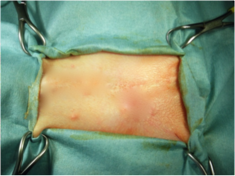

(5)ドレーピング

清潔な術野を確保するため、滅菌されたド レープで手術部位以外の範囲を覆います。

【4.手術 】

(1)手術中

滅菌器具を用いて、麻酔リスク、出血、痛み を最小限にするよう正確かつ迅速な手術を行 います。